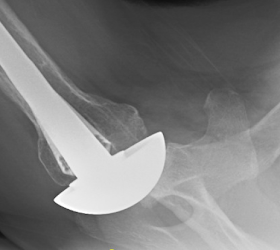

An active patient in his 40's presented with painful stiffness in his right shoulder and these x-rays showing severe glenohumeral arthritis and complete posterior decentering of the humeral head on the glenoid.

To avoid the risks and limitations of an anatomic total shoulder or a reverse total shoulder he elected to have a ream and run procedure. This was performed using an impaction grafted standard length humeral prosthesis with an anteriorly eccentric humeral head (see this link).